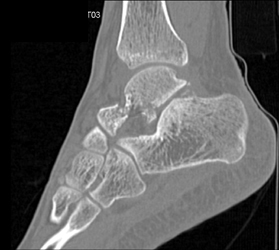

Diagnosis

Radius Fracture and Dislocation